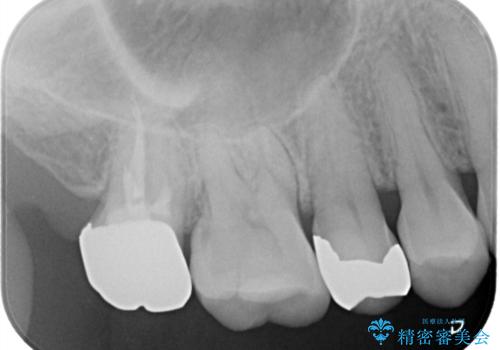

目立つ銀歯をセラミックに変えたい セラミックインレー

- 銀歯が気になるためやり替えたいとのことで来院されました。

セラミックインレーで治療を行いました。

口の中にチラつく銀歯は適合の良いセラミックインレーでやり替えることで綺麗にやり替えることができます。